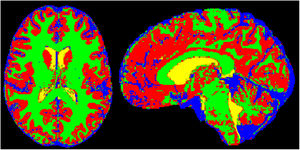

La cuantificación del volumen de LCR intracraneal extraventricular ha sido propuesta como un hallazgo útil para establecer el diagnóstico de HII (fig. 8). Alperin et al. han identificado el aumento de este volumen normalizado respecto al volumen total intracraneal, con un punto de corte de más del 18%, como un hallazgo radiológico que presenta una sensibilidad del 73% y una especificidad del 100%30.

Incremento del volumen de líquido cefalorraquídeo (LCR) extraventricular normalizado. Ejemplo de segmentación semiautomática de LCR extraventricular intracraneal en el que se demuestra la diferenciación del LCR intraventricular (en amarillo) del LCR extraventricular (azul). Sustancia gris y sustancia blanca segmentadas y diferenciadas en otros colores (rojo y verde, respectivamente).